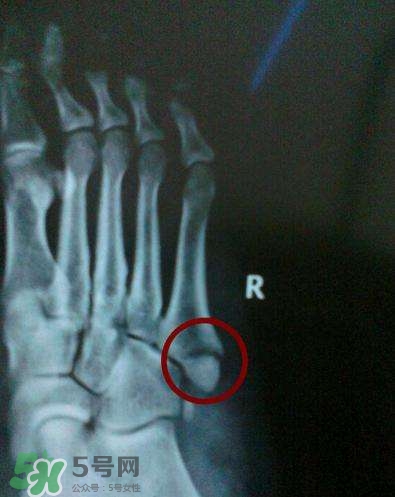

骨裂吃什么好得快?骨裂和骨折的区别

》的解答。1.骨折和骨裂吃什么最好2.骨裂吃什么好得快?骨裂和骨折的区别3.骨折好得最快的偏方骨裂吃什么4.骨裂吃什么好得快1.很多人出现骨裂的现象却没有重视,大家要知道骨裂的危害是很大的,如果不及时治疗会出现淤血,肿块,严重的还会引起感染,要想骨裂好的快可以多吃补肾的食物,因为中医上肾补好了,骨头也就强健了。